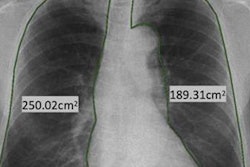

The company also plans to show its Altumira artificial intelligence software for radiography at RSNA 2019. Commercially released earlier this year, Altumira uses deep-learning algorithms to enhance the image quality of static and dynamic x-ray images.